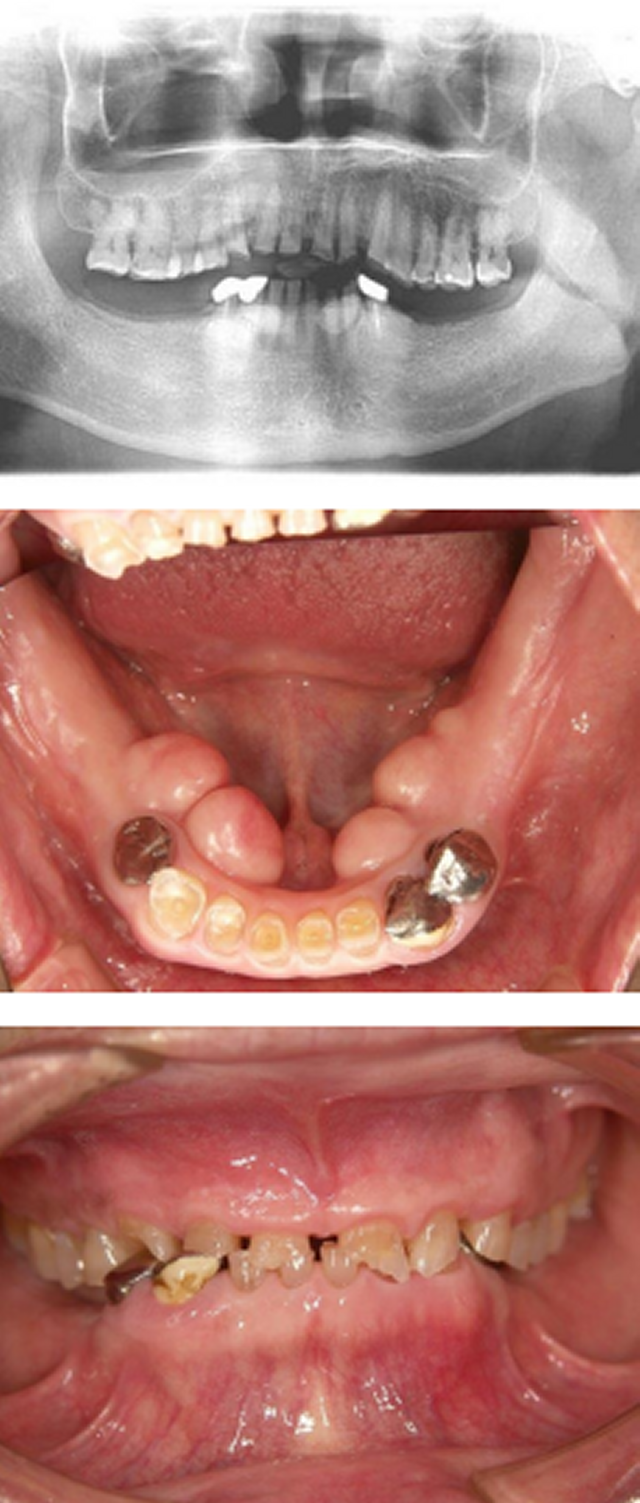

インプラント咬合改善症例

インプラント施術前

下あごの奥歯がなく、食いしばりが強いため前歯もすり減ってしまいました。

インプラント施術後

インプラントを6本埋入してかみ合わせも適当な高さに改善、前歯もセラミックをかぶせて見た目も改善しました。